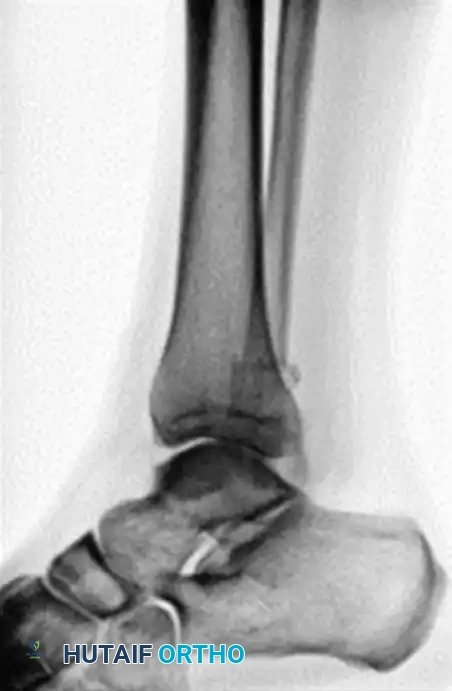

The following preoperative and postoperative radiographs demonstrate the successful application of augmented fixation in a young diabetic patient with a severe bimalleolar fracture-subluxation:

FIGURE 85-25 A and B: Preoperative radiographs of a highly unstable bimalleolar ankle fracture-subluxation in a 19-year-old man with a 12-year history of insulin-dependent diabetes mellitus.